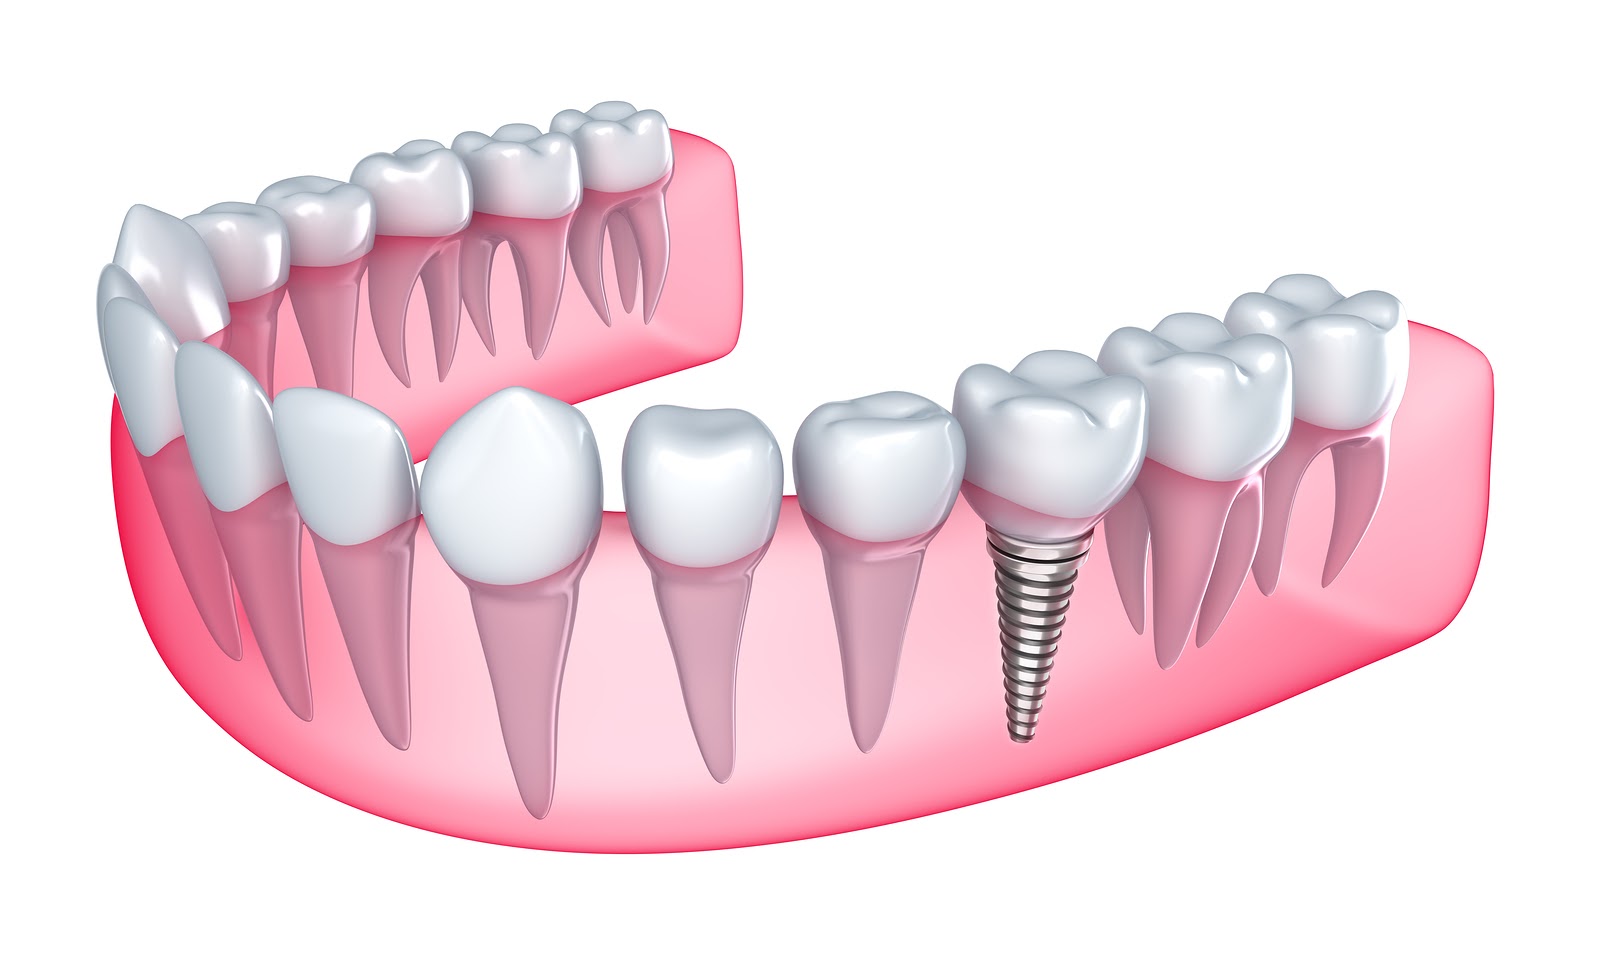

Dent Art Elazığ olarak odağımız, bilgi ve tecrübelerimizi hastalarımızın bireysel yararı ve sağlığı için kullanmaktır. Süt dişlerinden yirmilik dişlere, rutin kontrol muayenelerinden yüksek kaliteli dolgu ve kanal tedavilerine, karmaşık cerrahilere ve estetik tedavilere kadar ağız ve diş sağlığının her alanında tedaviler sunmaktayız.

1989 yılında Elbistanda doğdum.Mersinliyim. Liseyi Adana IMKB Anadolu Ogretmen Lisesinde okuduktan sonra 2008 yılında Gazi üniversitesi dis hekimliği fakültesine başladım. 2013 yılında dis hekimliğinde uzmanlık sınavını kazanarak Gazi üniversitesi agiz dis ve cene cerrahisi bolumunde uzmanlık eğitimine başladım.. Sonrasında Ankarada özel bir poliklinikte çalıştım. 2018- 2022 yılları arasında Elazığ’da özel polikliniklerde hastalarıma hizmet verdikten sonra Dent Art Ağız ve Diş sağlığı poliklinigini kurucu ortakları arasında yer aldım. Rubber dam uygulamalarıyla birlikte Estetik dolgu, kök kanal tedavileri; gömülü yirmi yaş çekimleri implant operasyonları sinus yükseltme ameliyatları ileri cerrahi teknikler apikal cerrahi preprotetik cerrahi botoks uygulamaları Temporomandibular eklem rahatsizliklari icin artrosentez uygulamalari ve protetik tedaviler yapmaktayım. Hastalarıma daha iyi hizmet sunabilmek için ulusal ve uluslararası konuşmacıların yer aldığı kurs, seminer ve sempozyumlara katıldım. Evli ve bir kız çocuk annesiyim.

Çalıştığım özel kliniklerde detertraj, Küretaj, diş eti çekilmesinin klinik ve cerrahi tedavisi, diş hekimliğinde lazer uygulamaları, implant ve kemik artırım operasyonları, botoks uygulamaları, gülüş tasarımı için diş eti düzenlemeleri, biyopsi, gömülü diş çekimi, sinüs lift işlemleri gibi birçok işlem uyguladıktan sonra 2022 yılında DentArt ağız ve diş sağlığı polikliniğinde kurucu ortaklarından biri olarak yer almaktayım

1989 yılında Elbistanda doğdum.Mersinliyim. Liseyi Adana IMKB Anadolu Ogretmen Lisesinde okuduktan sonra 2008 yılında Gazi üniversitesi dis hekimliği fakültesine başladım. 2013 yılında dis hekimliğinde uzmanlık sınavını kazanarak Gazi üniversitesi agiz dis ve cene cerrahisi bolumunde uzmanlık eğitimine başladım.. Sonrasında Ankarada özel bir poliklinikte çalıştım. 2018- 2022 yılları arasında Elazığ’da özel polikliniklerde hastalarıma hizmet verdikten sonra Dent Art Ağız ve Diş sağlığı poliklinigini kurucu ortakları arasında yer aldım. Rubber dam uygulamalarıyla birlikte Estetik dolgu, kök kanal tedavileri; gömülü yirmi yaş çekimleri implant operasyonları sinus yükseltme ameliyatları ileri cerrahi teknikler apikal cerrahi preprotetik cerrahi botoks uygulamaları Temporomandibular eklem rahatsizliklari icin artrosentez uygulamalari ve protetik tedaviler yapmaktayım. Hastalarıma daha iyi hizmet sunabilmek için ulusal ve uluslararası konuşmacıların yer aldığı kurs, seminer ve sempozyumlara katıldım. Evli ve bir kız çocuk annesiyim.

Çalıştığım özel kliniklerde detertraj, Küretaj, diş eti çekilmesinin klinik ve cerrahi tedavisi, diş hekimliğinde lazer uygulamaları, implant ve kemik artırım operasyonları, botoks uygulamaları, gülüş tasarımı için diş eti düzenlemeleri, biyopsi, gömülü diş çekimi, sinüs lift işlemleri gibi birçok işlem uyguladıktan sonra 2022 yılında DentArt ağız ve diş sağlığı polikliniğinde kurucu ortaklarından biri olarak yer almaktayım

Üst düzey işlemler yapabilen ve gelişen teknolojilerle uyumlu tüm yenilikçi dental uygulamaları profesyonel olarak sunuyoruz

Hastalarımızın ağız ve diş sağlıklarını koruyarak yaşamları boyunca sağlıklı ve işlevsel bir gülümsemeye sahip olmalarını sağlıyor, hasta memnuniyetini ve rahatını en ön planda tutarak mükemmel, sürdürülebilir ağız ve diş sağlığı hizmetleri sunuyoruz.

Gülüşünüzü Tekrar Canlandırıyoruz